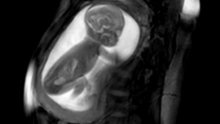

تقنية تصوير تساعد في تشخيص أمراض قلب الأجنة

توصل باحثون لطريقة تساعد في تشخيص أمراض القلب لدى الأجنة وعلاجها فور ولادة الطفل، وذلك عن طريق التقاط صور لقلب الجنين وهو ينبض داخل رحم الأم، حيث يتم فحص النساء الحوامل بجهاز تصوير الرنين المغناطيسي وأجهزة كمبيوتر فعالة تستطيع رسم نماذج ثلاثية الأبعاد، لقلوب الأجنة الصغيرة، وذلك وفقا لموقع BBC.